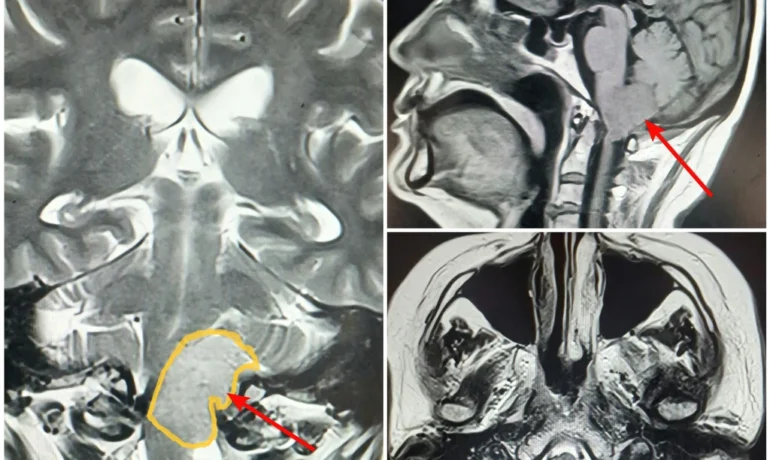

Менингиома краниовертебрального перехода — редкая и технически сложная патология, требующая высокой точности и большого опыта со стороны нейрохирургической команды. Данная анатомическая область головного мозга считается...